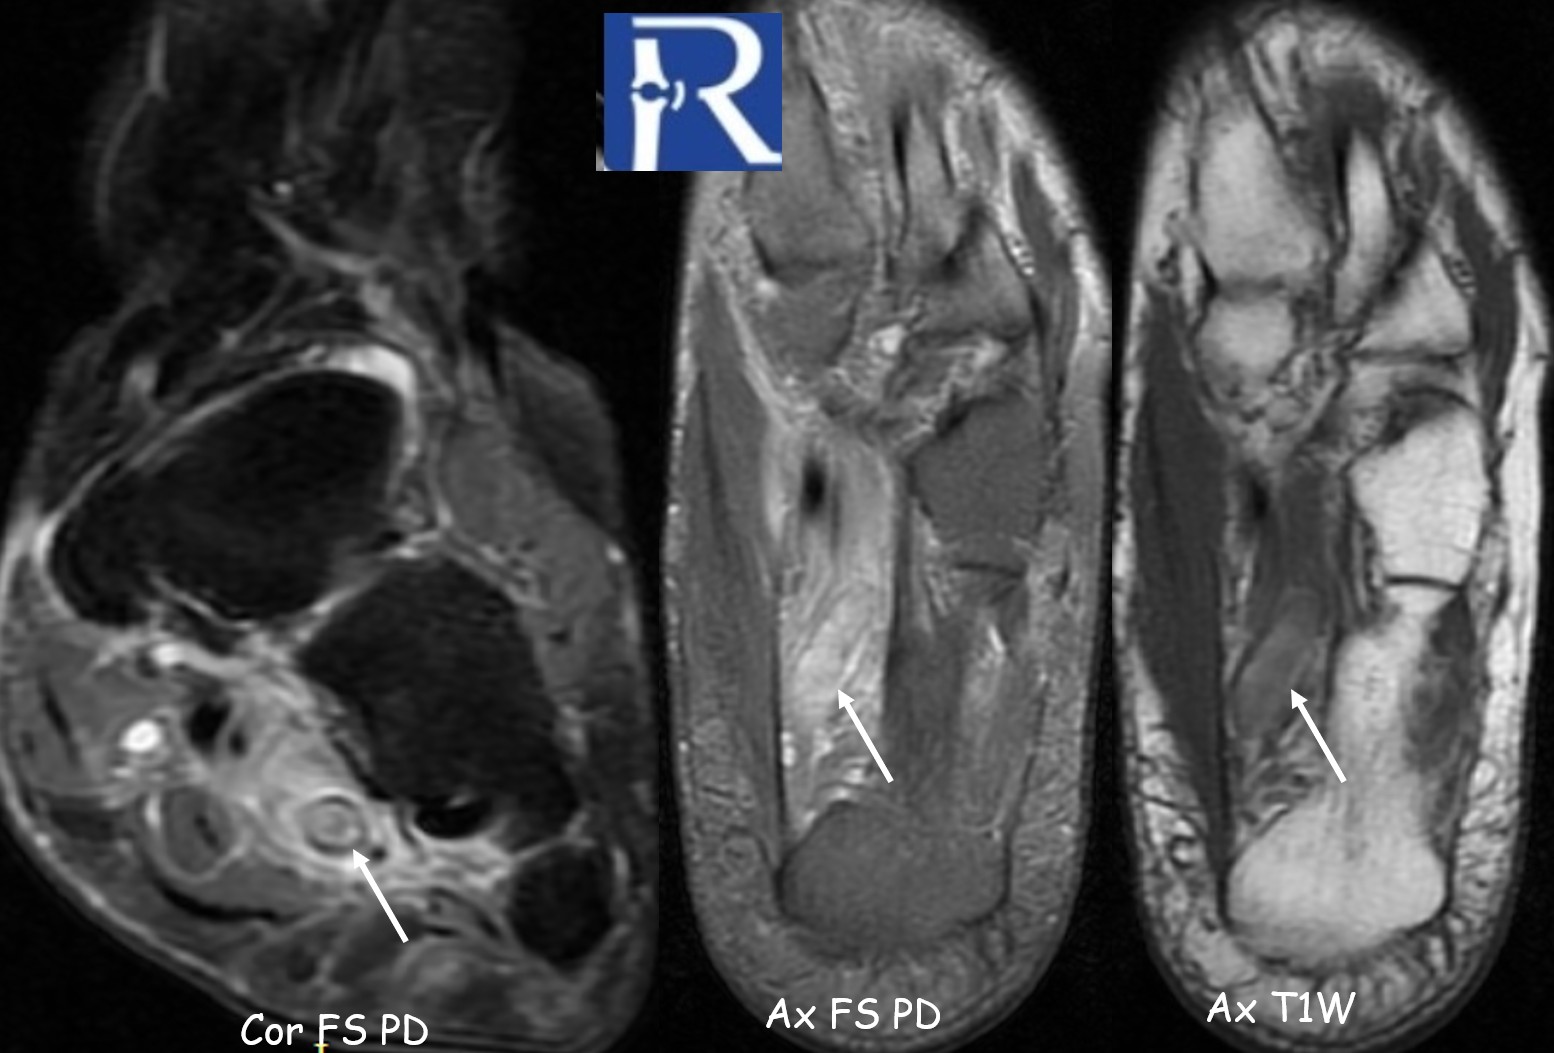

MRI of the left ankle demonstrated:

- Loss of normal venous flow void in the lateral plantar vein

- Venous dilatation

- T1 hyperintense intraluminal signal compatible with subacute thrombus

- Hyperintense thrombus on proton density fat-suppressed sequences

- Prominent perivascular soft tissue edema extending into adjacent musculature

Perivascular edema was the most conspicuous indirect sign.